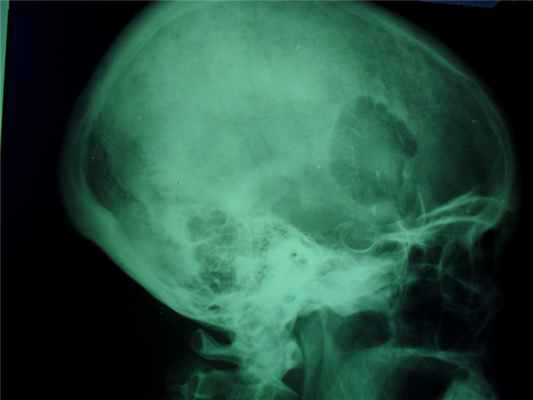

Различают губчатую остеому, остеому, состоящую из коркового и губчатого вещества, и остеому из сплошного компактного вещества. Первые два вида наблюдаются на длинных трубчатых костях, компактные остеомы поражают плоские кости черепа.

Рентгенодиагностика спонгиозной и медуллярной остеомы:

- остеома всегда солитарна,

- форма шаровидная, шиповидная,

- опухоль сидит на кости на широкой правильной ножке,

- корковый слой при остеоме не нарушен.

- контуры гладкие, ровные,

- губчатая сеть кости и опухоли непрерывно переходит друг в друга.

Рентгенодиагностика компактной остеомы:

- округлая, шаровидная или яйцевидная форма,

- опухоль дает гомогенную бесструктурную тень.

Это сосудистая опухоль, исходит из костного мозга тех костей, которые содержат красный костный мозг, может наблюдаться в любом возрасте и не зависит от пола, излюбленная локализация тела позвонков и плоские кости черепа, протекают бессимптомно.

При локализации гемангиомы в плоских костях свода черепа происходит:

- вздутие кости и разрушение коркового слоя, надкостница приподнимается опухолью,

- характерен структурный рисунок – из центра опухоли к ее поверхности лучеобразно или веерообразно рассыпаются тонкие и более грубые костные балки.